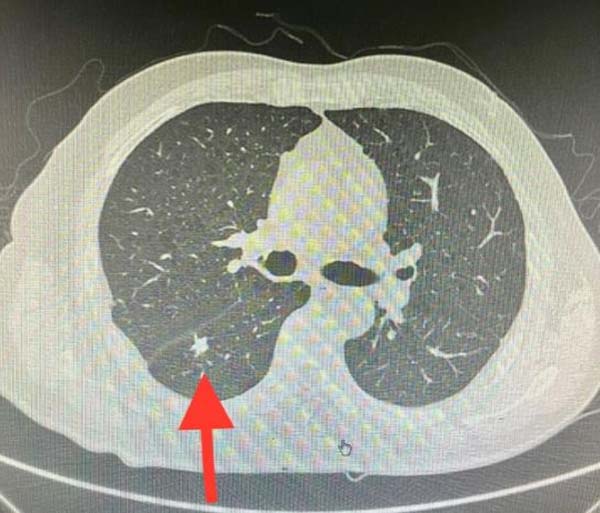

患者40天前因咳嗽出现了右侧胸部的撕裂样疼痛,后逐渐出现呼吸费力,当地医院查胸部CT见右侧气胸,右肺外压性不张,置入右侧胸腔引流管,半月后气胸好转拔管出院,后反复出现气胸。期间查胸部CT见右肺下叶背段结节,考虑肺癌可能。

入院后完善检查,胸部CT显示右肺下叶背段实性结节,边缘毛刺,形态不规则,高度考虑恶性病变可能。